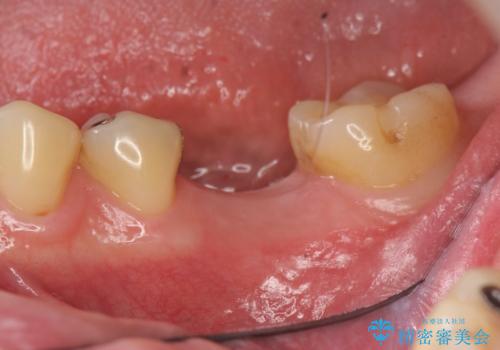

- 銀歯の奥歯で噛むと違和感・痛みがあるとのことで検査・治療を求めて来院されました。

銀歯を除去して見ると内部で虫歯が再発し、歯の辺縁は破折し保存が難しく抜歯をしなければいけない状態でした。